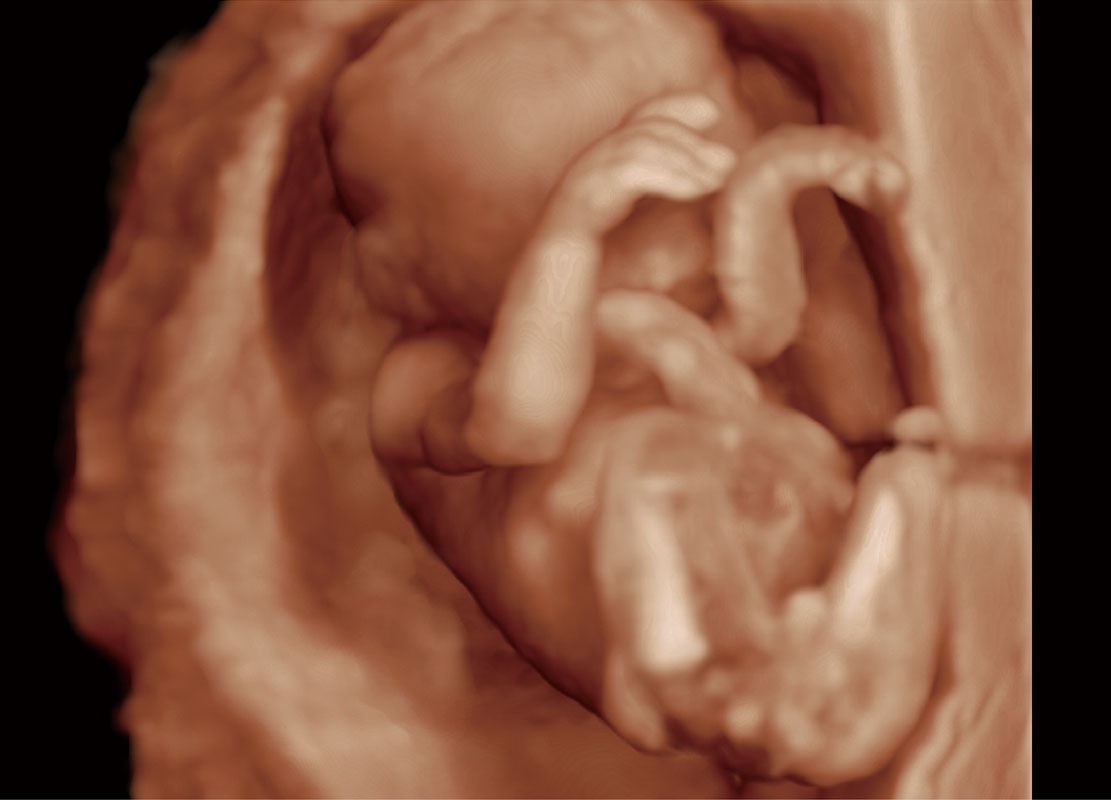

早孕筛查

P60在胎儿早孕期超声筛查中为您带来优异的图像质量。

• 高分辨率容积成像-早孕胎儿